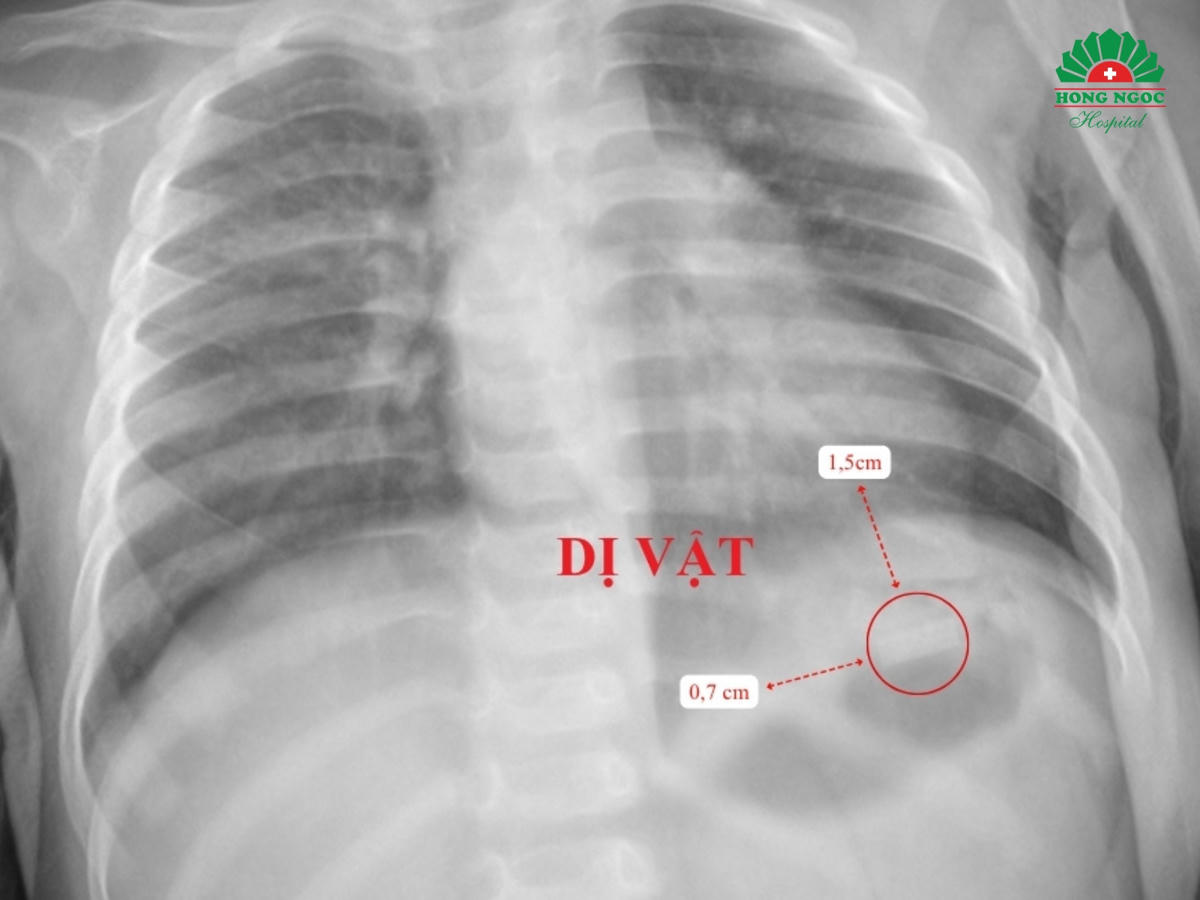

Ngay sau khi phát hiện, bé có biểu hiện ho sặc, đỏ mặt, nôn ra tàn thuốc, được đưa đến bệnh viện trong trạng thái lo lắng. Kết quả X-quang và siêu âm cho thấy dị vật hình chữ nhật kích thước 1,5x0,7 cm nằm ở vùng hạ sườn trái, vị trí bóng hơi dạ dày. Bác sĩ xác định dị vật mỏng, có góc nhọn, nguy cơ cao gây thủng ruột, đồng thời bé có dấu hiệu say thuốc lá nhẹ do nuốt phải phần thuốc còn nicotine.